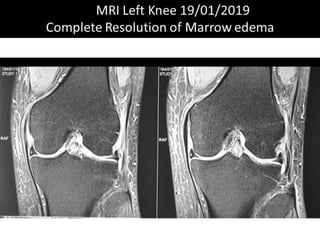

The document presents a detailed case study of a patient with transient osteoporosis of the hip (TOH) and spontaneous osteonecrosis of the knee (SONK) treated at Choithram Hospital & Research Centre in India. Over 20 years, the patient experienced multiple episodes of TOH and SONK with no history of trauma or co-morbidities, resulting in resolutions and recurrences of conditions. The information is intended for orthopedic surgery students and highlights personal experiences and case collections, with a disclaimer regarding content usage and potential controversies.